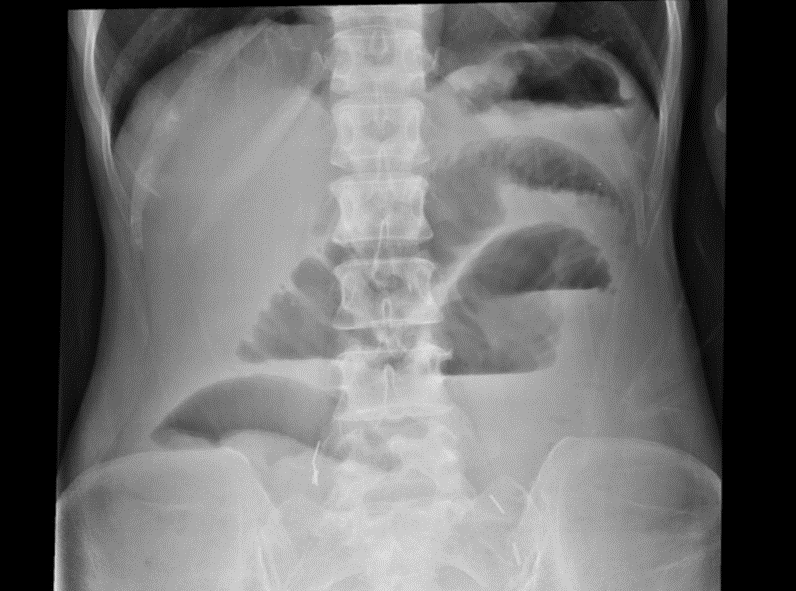

突然ですが、レントゲンクイズを出題します。画像の所見を読んで、離床の注意点を説明してください。

[クイズ解答例]

細かいひだの小腸ガスの貯留と、小腸の拡張がみられ、腸閉塞が疑われるため、離床は立ち止まり腸閉塞に対する治療・コントロールを優先すべきと考えられます。

上記講座では、腸閉塞の画像読影について詳しい解説があります。